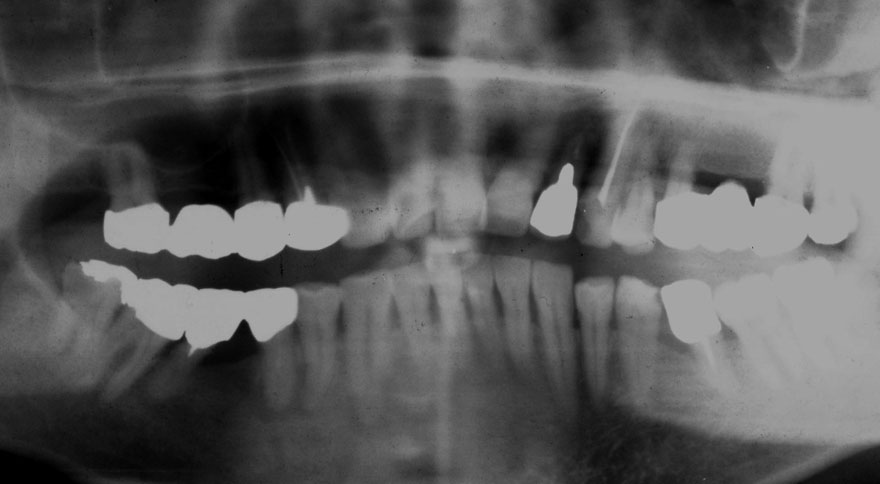

初診時 54歳 女性

河田歯科医院

22年後 76歳